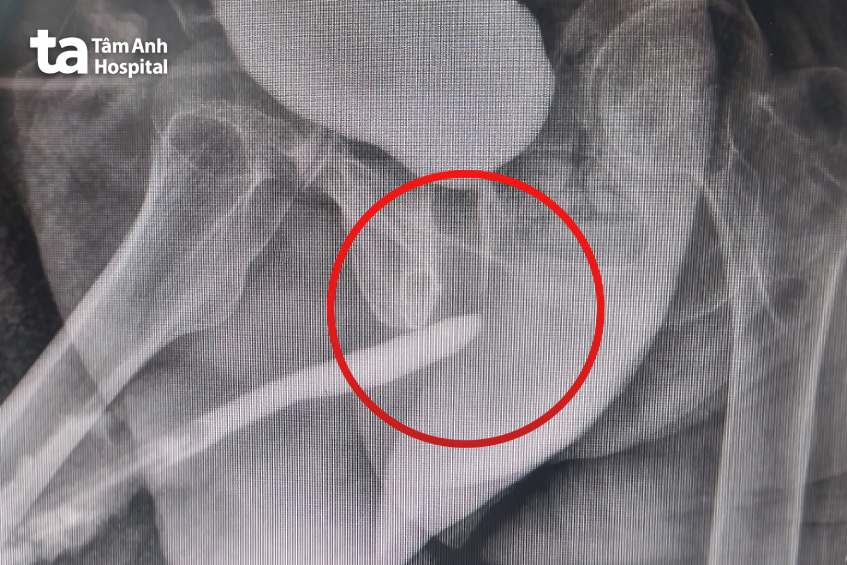

Bác sĩ chuyên khoa I Phạm Thế Anh, khoa Tiết niệu, Trung tâm Tiết niệu – Thận học – Nam khoa, Bệnh viện Đa khoa Tâm Anh TP.HCM, chỉ định nội soi bàng quang cho người bệnh, phát hiện niệu đạo của ông hẹp bít hoàn toàn không có kẽ hở. Hình ảnh X-quang niệu đạo ngược dòng ghi nhận đoạn hẹp chỉ 0,5cm, nằm ở phần niệu đạo sau (gần bàng quang).

Bác sĩ Thế Anh đánh giá đoạn hẹp niệu đạo ngắn, trong khi phần niệu đạo còn lại bình thường, nên có thể điều trị bằng phẫu thuật tạo hình niệu đạo cắt nối tận – tận.